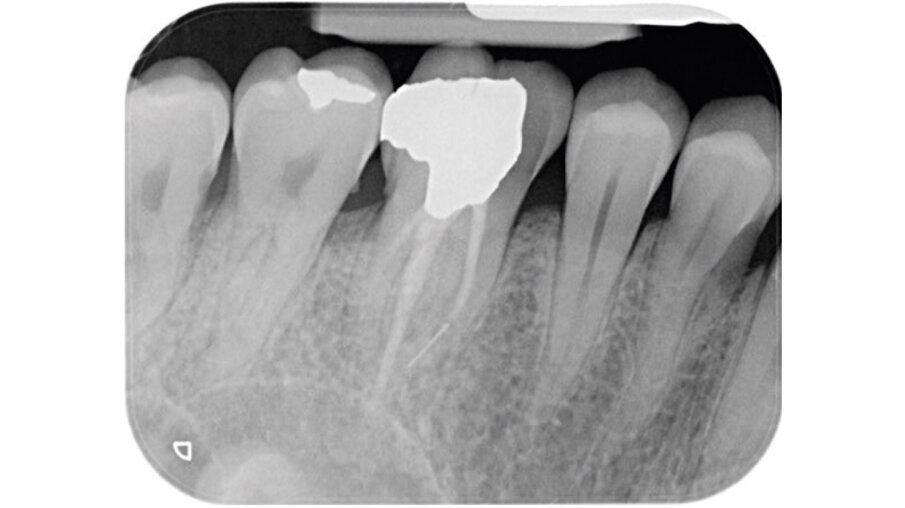

Un paziente maschio (ASA I), senza patologie croniche sistemiche e non fumatore, è stato sottoposto all’estrazione dell’elemento 16 a seguito del fallimento di terapie endodontiche e dell’impossibilità di eseguire un restauro coronale (Figg. 1a, 1b). Nella selezione del paziente sono stati criteri di esclusione: pregressa radioterapia nel distretto testa/collo, assunzione di farmaci che possano indurre ONJ, disordini ematici coagulativi, bruxismo, scarsa igiene orale domiciliare, occlusione instabile, carie non trattate, malattia parodontale non controllata, denti adiacenti a quelli da estrarre con mobilità di grado I o superiore, aspettative di risultato irreali, impossibilità o non propensi a tornare ai controlli di routine e di follow-up. La situazione dei tessuti è stata valutata pre-operatoriamente tramite radiografia periapicala (Fig. 1c) (VistaScan Mini Plus, Dürr Dental). Tramite la CBCT pre-operatoria è stato possibile fare una programmazione implantare. Sulla base dell’anatomia coronale è stata definita la posizione implantare (OnDemand3D, Cybermed), da questa analisi sono stati decisi anche il diametro e la lunghezza dell’impianto.

Fig. 1c - Radiografia con cura canalare non ritrattabile, strumento rotto e probabile frattura verticale con sintomatologia da parte del paziente.